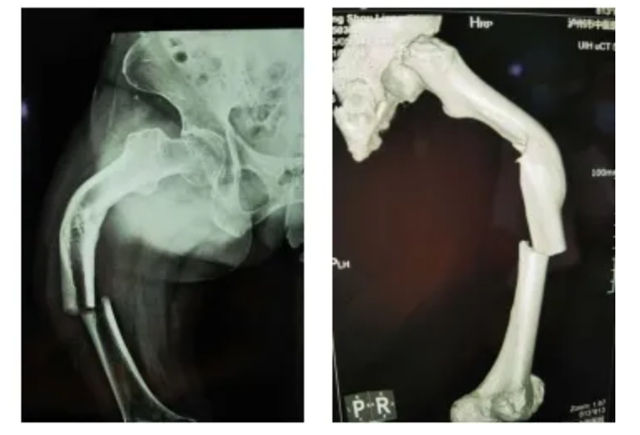

(股骨中段断裂,上端有明显畸形)

当她的X光片出来时,收治的医生都被她的伤情吓了一跳。原来此次她骨折的上端还有一处骨伤畸形愈合。这是什么情况呢?

原来,张守莲在三年前还摔伤过一次,当时在一家医院进行了手法复位,但因操作不当,没能复位成功,留下了后遗症。三年来她都是以拄拐行走。